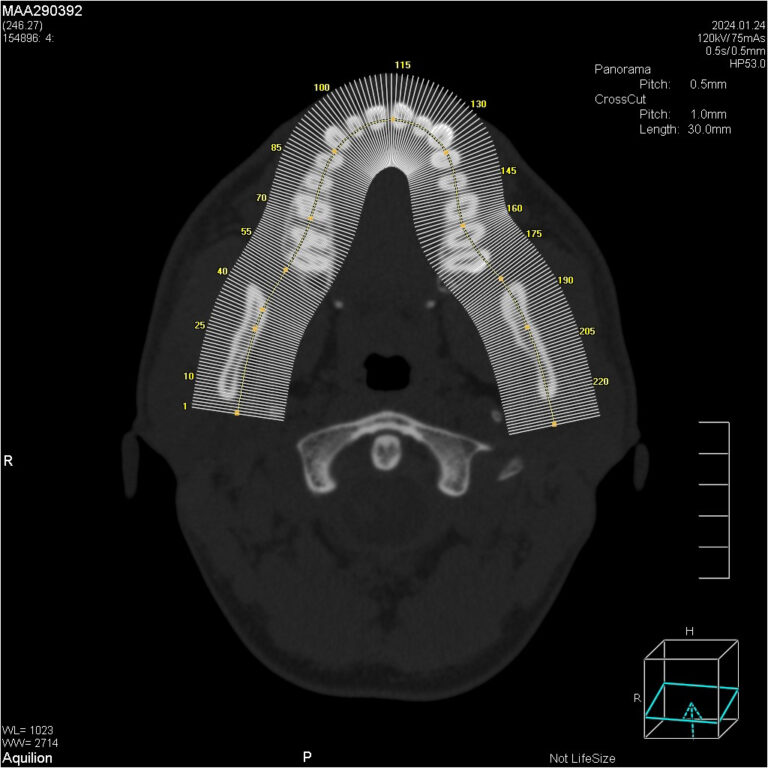

Мультиспиральный томограф выполняет послойное сканирование области верхней и нижней челюстей с помощью рентгеновских лучей, а затем, используя компьютерную обработку данных, создает 3D-модели исследуемой зоны. Современные модели томографов проводят круговое сканирование по спирали, делая срезовые снимки на расстоянии 0,5 мм друг от друга. Затем на основе этих данных реконструируются детальные изображения челюстно-лицевой области в трехмерном формате.

Исследование занимает всего пару минут. Данные, полученные при сканировании, проходят цифровую обработку и выводятся на монитор компьютера в виде 3D-изображений. Врач-рентгенолог внимательно анализирует данные и выдает заключение.